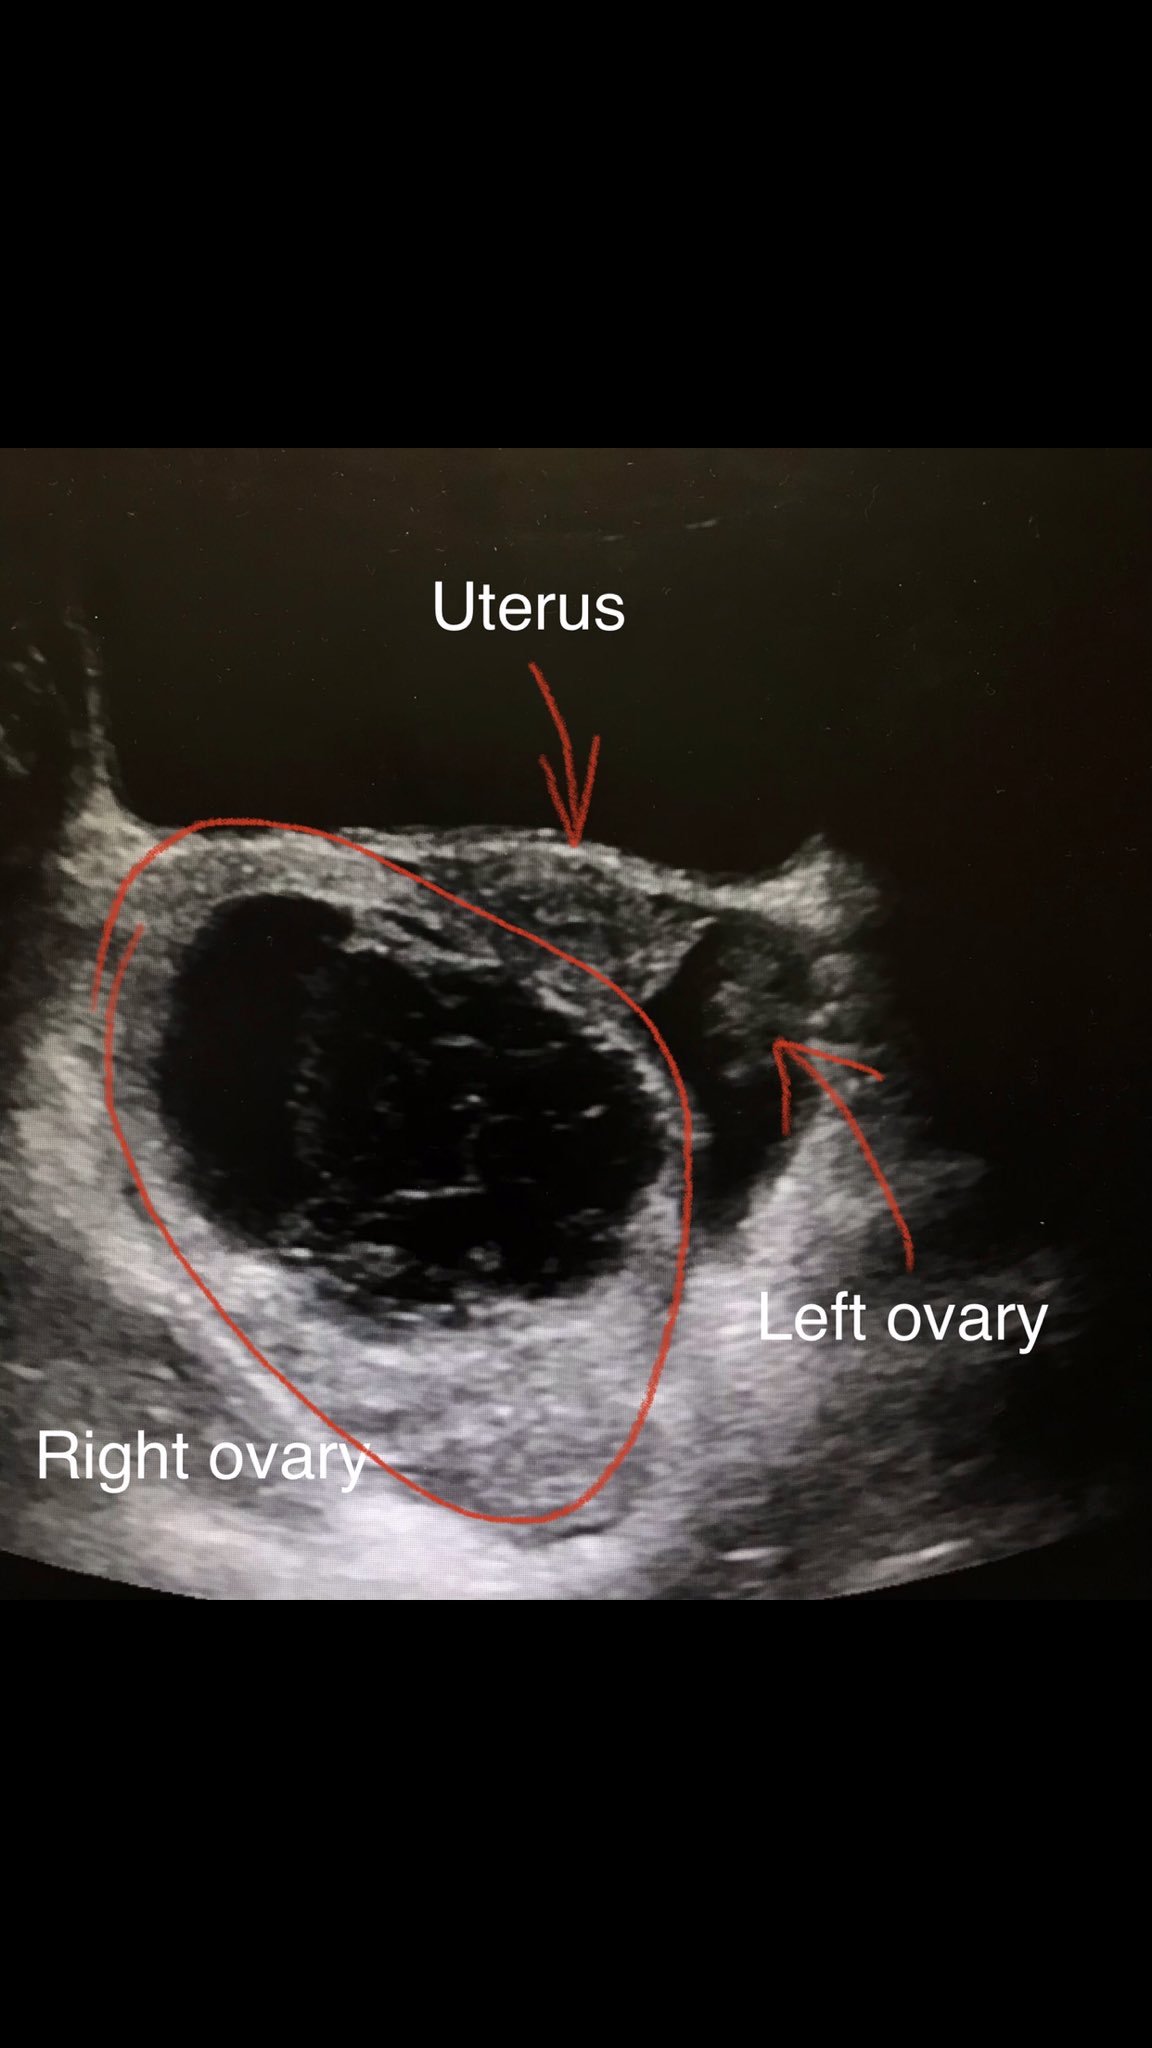

What Is Considered Enlarged Ovary. Web an enlarged ovary is one that has become larger than normal. Ovaries can be different sizes for different people and change size during the monthly. Simply put, this condition makes one ovary larger than the other and may cause a variety of other mild to severe symptoms. However, in some cases, it may be a sign of an underlying medical condition. Web an enlarged ovary can be a common occurrence during the menstrual cycle, and it is often harmless. 6 causes of enlarged ovaries. You may have an enlarged ovary if a cyst Web polycystic ovary syndrome (pcos) is a common condition that affects how a woman's ovaries work. While some causes of enlarged ovaries are harmless, some can pose a real health threat. Web how big is an ovary? Some women might experience swelling of the ovary or ovaries without any side effects at all while others may suffer cramps and other forms of discomfort. There are many different causes of enlarged ovaries and they have varying degrees of severity. Web what causes an enlarged ovary? Web what is an enlarged ovary? Read on to find out.

Ovaries can be different sizes for different people and change size during the monthly. 6 causes of enlarged ovaries. Some women might experience swelling of the ovary or ovaries without any side effects at all while others may suffer cramps and other forms of discomfort. You may have an enlarged ovary if a cyst Web what is an enlarged ovary? Web how big is an ovary? There are many different causes of enlarged ovaries and they have varying degrees of severity. Web polycystic ovary syndrome (pcos) is a common condition that affects how a woman's ovaries work. Simply put, this condition makes one ovary larger than the other and may cause a variety of other mild to severe symptoms. However, in some cases, it may be a sign of an underlying medical condition.

What Is Considered Enlarged Ovary Web what is an enlarged ovary? 6 causes of enlarged ovaries. While some causes of enlarged ovaries are harmless, some can pose a real health threat. Some women might experience swelling of the ovary or ovaries without any side effects at all while others may suffer cramps and other forms of discomfort. Web what is an enlarged ovary? However, in some cases, it may be a sign of an underlying medical condition. You may have an enlarged ovary if a cyst Web an enlarged ovary can be a common occurrence during the menstrual cycle, and it is often harmless. Web what causes an enlarged ovary? Web how big is an ovary? Web an enlarged ovary is one that has become larger than normal. Simply put, this condition makes one ovary larger than the other and may cause a variety of other mild to severe symptoms. Read on to find out. Web polycystic ovary syndrome (pcos) is a common condition that affects how a woman's ovaries work. There are many different causes of enlarged ovaries and they have varying degrees of severity. Ovaries can be different sizes for different people and change size during the monthly.